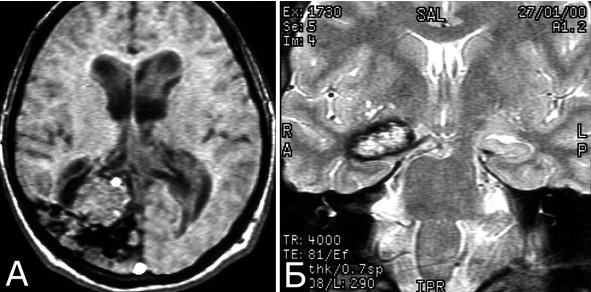

Скорость регресса очаговых симптомов, обусловленных кровоизлиянием, может быть различна и также зависит от его объема и локализации. Длительный регресс и остаточные симптомы более типичны для кровоизлияний из глубинных каверном. Более полное восстановление неврологического дефекта отмечается, как правило, после первого кровоизлияния. При повторных кровоизлияниях из каверном глубинной локализации нередко остается стойкий неврологический дефицит (рис. 34).

Данное наблюдение демонстрирует непредсказуемость и интервалов между кровоизлияниями и возможность большой длительности интервалов между ними (см. ниже). Оно также интересно тем, крупная киста сформировалась, судя по ее рентгенологическим характеристикам, задолго до последнего клинического эпизода, а появившаяся выраженная симптоматика обусловлена небольшим по объему кровоизлиянием во внутреннюю капсулу.

Рис. 34. Б-ной Т-ко, 1950 г. р. Кавернозная мальформация наружных отделов зрительного бугра с крупной постгеморрагической кистой в области внутренней капсулы и базальных ганглиев слева. Рецидивирующие кровоизлияния. А, Б – МРТ, режимы Т1, Т2, аксиальная проекция, В – КТ без контрастного усиления. Объяснения в тексте

Течение заболевания (б-ной Т-ко, 1950 г. р.): в 1981 г (32 г) в течение нескольких дней появилась и наросла слабость в правых конечностях, которая полностью регрессировала через 3 мес. Лечился с диагнозом «инсульт». При АГ патологии не выявлено. Повторные аналогичные эпизоды в 1989 г (39 лет) и 1998 (48 лет), также с полным регрессом неврологического дефекта. 1.10.2008 (58 лет) остро развился глубокий правосторонний гемипарез, правосторонняя гемигипестезия, моторная афазия. При КТ и МРТ спустя 1 неделю после этого эпизода (ранее эти исследования не проводились) выявлена небольшая КМ наружных отделов левого зрительного бугра, большая кистозная полость, распространяющаяся на внутреннюю капсулу и базальные ганглии) (А – В), признаки небольшого кровоизлияния в проекции внутренней капсулы (В, стрелка). При поступлении спустя месяц после кровоизлияния: выраженная моторная афазия; центральный парез VII нерва справа; выраженная болевая гипестезия на правой половине лица; глубокий пирамидный правосторонний гемипарез, но может передвигаться самостоятельно; глубокая правосторонняя болевая гемигипестезия; нарушение суставно-мышечного чувства в дистальных отделах конечностей справа. Операция: опорожнение кисты и удаление КМ глубинных отделов левого полушария. Послеоперационное течение: без ухудшения. Гистологический диагноз: кавернозная мальформация с гиалинозом стромы и склерозом отдельных полостей.